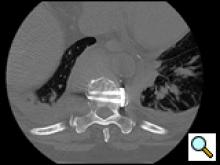

The thoracic spine can be approached through the right or left chest and communication with the spine surgeon is mandatory so that the approach and extent of exposure can be tailored appropriately. In the absence of lateralizing pathology, either a right or left-sided thoracotomy can be used to expose the thoracic spine. As a general rule, the upper thoracic spine (T2-9) is better approached from the right side because of the location of the heart, aortic arch and great vessels. Conversely, in the case of the thoracolumbar spine (T10-L2) a left-sided thoracotomy is preferred to avoid liver retraction. The side of approach must provide maximum exposure to the pathology to be treated. Local factors such as previous thoracotomy, pleurodesis, or infection should also be considered. In general, a right sided approach provides more direct access to the spine, as the mediastinal structures lie to the left of the vertebral bodies. CT and MRI allow for a precise evaluation of the anatomy of the spine pathology and the related intra-thoracic structures (Figures 1a, 1b).